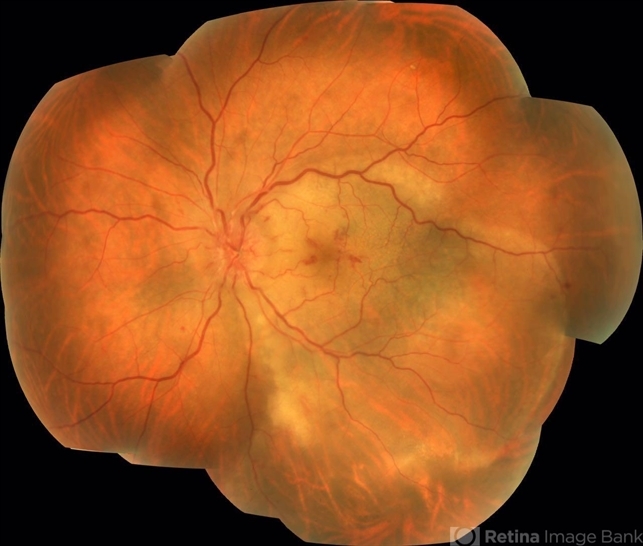

- acute syphilitic posterior placoid chorioretinitis

- Claudio Zett Lobo, UNIFESP

- Fundus camera

- 66-year-old woman with acute visual acuity loss.